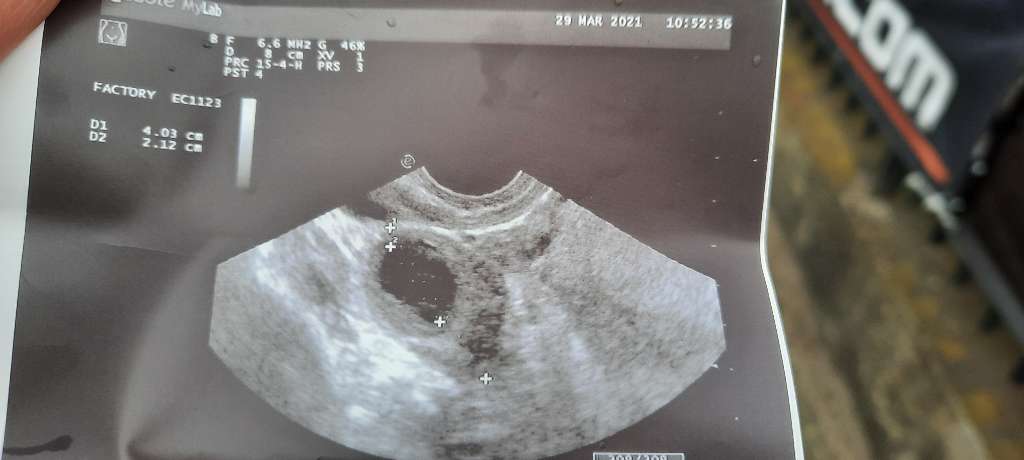

6t 5dKtóry tc? Był pęcherzyk żółtkowy? Głowa do góry, wszystko może się jeszcze pokazać![]()

Jeszcze niestety nie ma zarodka jest sam pecherzyk ciazowy